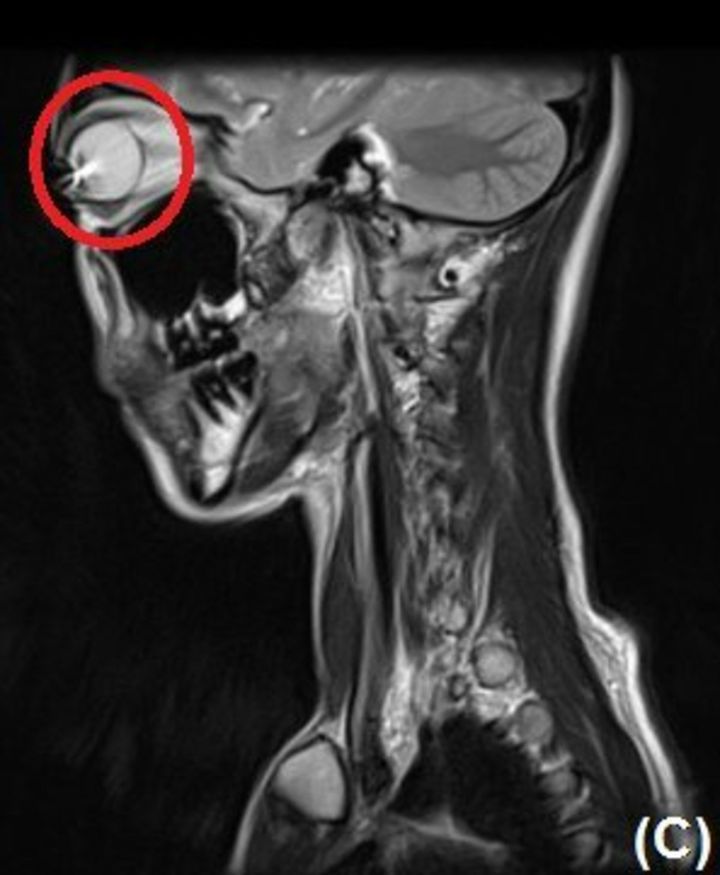

意外と知られていないのか、カラコンしながらMRIは撮れません。そのためか「ケースがない!」という人がいます。再利用するならケースを持ってきて下さい。カラコンの色がついている所には、酸化鉄や酸化チタンが含まれています。カラコンをつけたままMRIを撮ると、目の表面に傷が付くかもしれません。 X「ドクターK@眼科医パパ」(https://x.com/doctorK1991/status/2008867855929114845,2026年1月13日最終閲覧)

実はカラコンをつけたままのMRIはとても危険です。カラコンの色がついている部分には、酸化鉄、酸化チタンといった金属成分が含まれています。MRIは強力な磁場を使う検査です。そのため、これらの成分が影響を受ける可能性があるのです。そのため、検査直前に外すことになり、「再利用したいのにケースがない」という人が一定数いるそうです。

カラコンをつけたままMRIを撮影すると目の表面に傷が付くおそれがあるとのこと。検査後にまた使いたい人は必ずケースを持参するのがおすすめですよ。